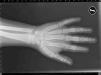

Pacientes y métodosCaso 1Varón de 9 años, hijo de padres sanos, no consanguíneos. Presentó hiperbilirrubinemia en el periodo neonatal. Estudiado por primera vez a los 2 años de edad por calcificaciones subcutáneas en antebrazos, abdomen, muslos y piernas. La exploración física reveló obesidad, cara redonda, cuello corto y manos pequeñas (fig. 2). Sin desarrollo puberal, peso 20kg (DE 3,2), talla 90cm (DE –1,1), índice de masa corporal (IMC) 24,7 (DE 6,9), lesiones máculo-papulosas induradas en el tronco y las extremidades. Bioquímica en sangre: calcio (Ca) total 9,3mg/dl (rango normal 8,8-10,8); Ca iónico 4,9mg/dl (4,9-5,5); fósforo (P) 5,6mg/dl (2,9-5,1); PTH intacta 830 pg/ml (0-68,2); tiroxina T4 libre (T4L) 0,9 ng/dl (0,7-2,0) y TSH 2,9μU/ml (0,49-4,67). Tomografía computarizada cerebral (TCC) normal. A los 8 años de edad presenta disminución de los niveles de Ca total (8,1mg/dl) y Ca iónico (4,36mg/dl) y aumento de niveles de P (6,7mg/dl) y PTH (1.716 pg/ml); el calcitriol 56 pg/ml (normal 16-56) y la T4L (0,8 ng/dl) fueron normales, y la TSH fue elevada (9,7μU/ml). La TCC muestra pequeñas calcificaciones en plexos coroideos. No han aparecido nuevas calcificaciones subcutáneas. En la radiografía de mano izquierda se observa braquidactilia, osteoporosis y aceleración de la edad ósea (edad ósea, 12 años; edad cronológica, 9 años) (fig. 3). Se realiza diagnóstico clínico de PHP-Ia e hipotiroidismo e inicia tratamiento con L-tiroxina, calcio y calcitriol, con normalización de las cifras de Ca, P, T4L y TSH, mientras que la PTH persiste elevada.